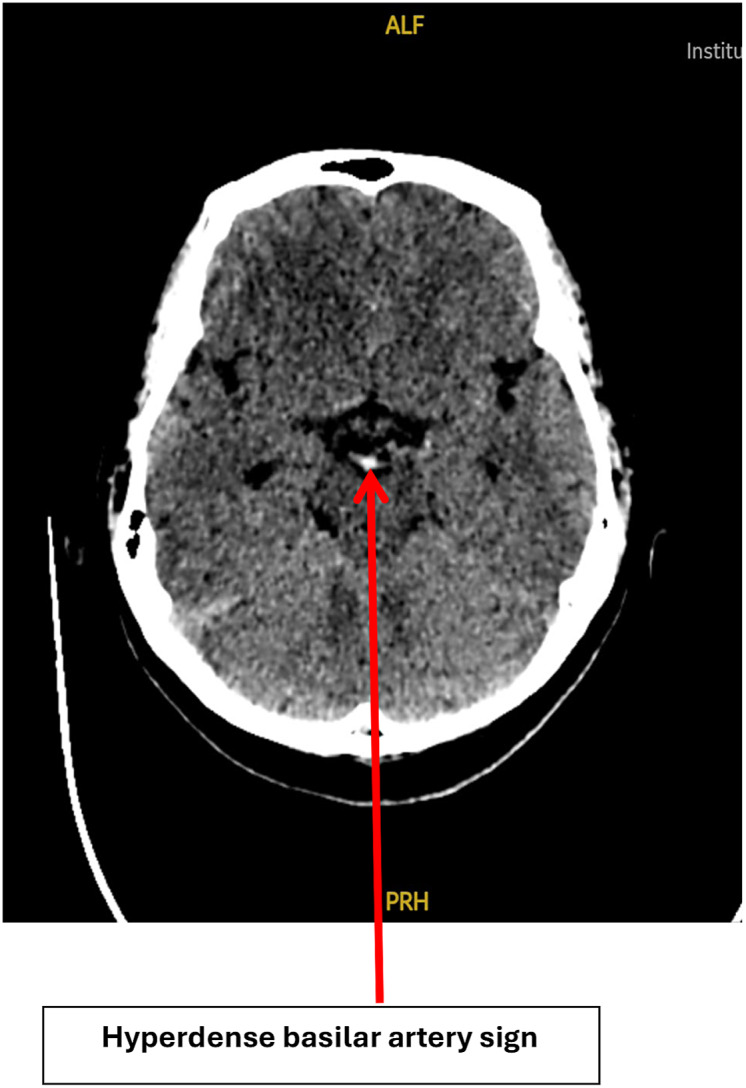

Introduction: This case report illustrates the complexities of arrhythmogenic right ventricular cardiomyopathy (ARVC) and its thromboembolic complications resulting in top-of-basilar artery syndrome. We discuss the case of a 37-year-old male with ARVC who presented with acute onset of dizziness, imbalance, and vomiting, leading to the diagnosis of a top-of-basilar artery occlusion (BAO) which was successfully treated.

Case presentation: This case highlights the diagnostic and acute treatment challenges in BAO due to its non-specific symptoms and emphasizes the critical role of CT angiography in detecting occlusive thrombi for timely intervention. With prompt endovascular thrombectomy and bridging intravenous thrombolysis, complete recanalization was achieved and the patient was discharged with modified Rankin Scale (mRS) of 1. Effective management strategies involve assessing ventricular function, detecting arrhythmias, identifying intracardiac thrombi, and implementing individualized stroke prevention measures, such as using direct oral anticoagulants.